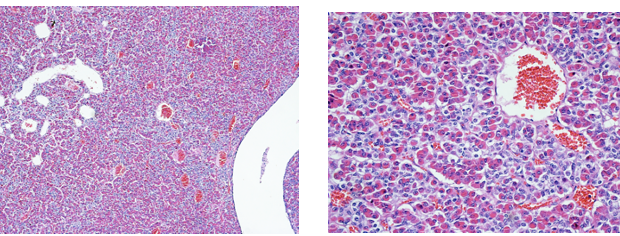

Follicles

Red arrow –> follicular cells

Black cells –> C cells

Thyroid colloid